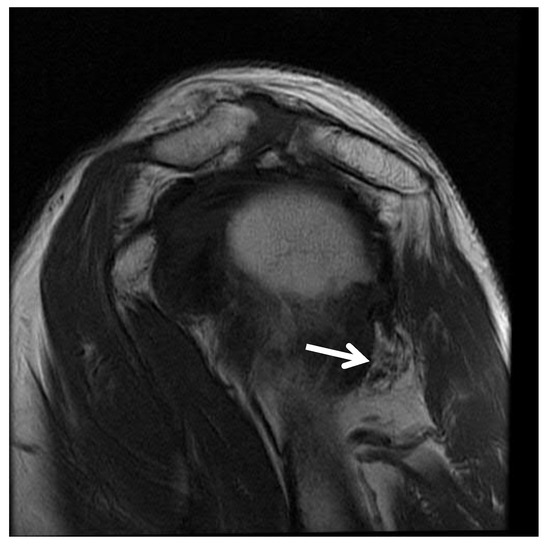

- Sanders, T.G.; Tirman, P.F. Paralabral cyst: An unusual cause of quadrilateral space syndrome. Arthroscopy 1999, 15, 632–637. [Google Scholar] [CrossRef] [PubMed]

- Robinson, P.; White, L.M.; Lax, M.; Salonen, D.; Bell, R.S. Quadrilateral space syndrome caused by glenoid labral cyst. AJR Am. J. Roentgenol. 2000, 175, 1103–1105. [Google Scholar] [CrossRef] [PubMed]